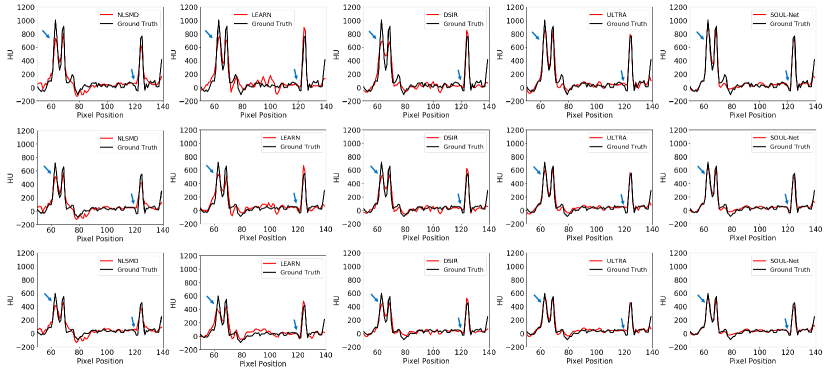

Fig. 5 shows the horizontal profiles of different results along the blue dashed line in the first row of Fig. 2. Two blue arrows indicate two sharp areas that can distinguish the ability in edge preservation for different methods . It is obvious that the proposed SOUL-Net has the closest results to the reference and achieves higher reconstruction accuracy than other methods. This is consistent with the results of our visual inspection.